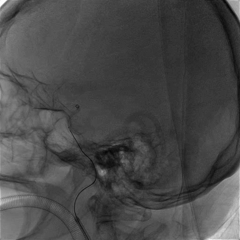

NeuroHawk Case 2